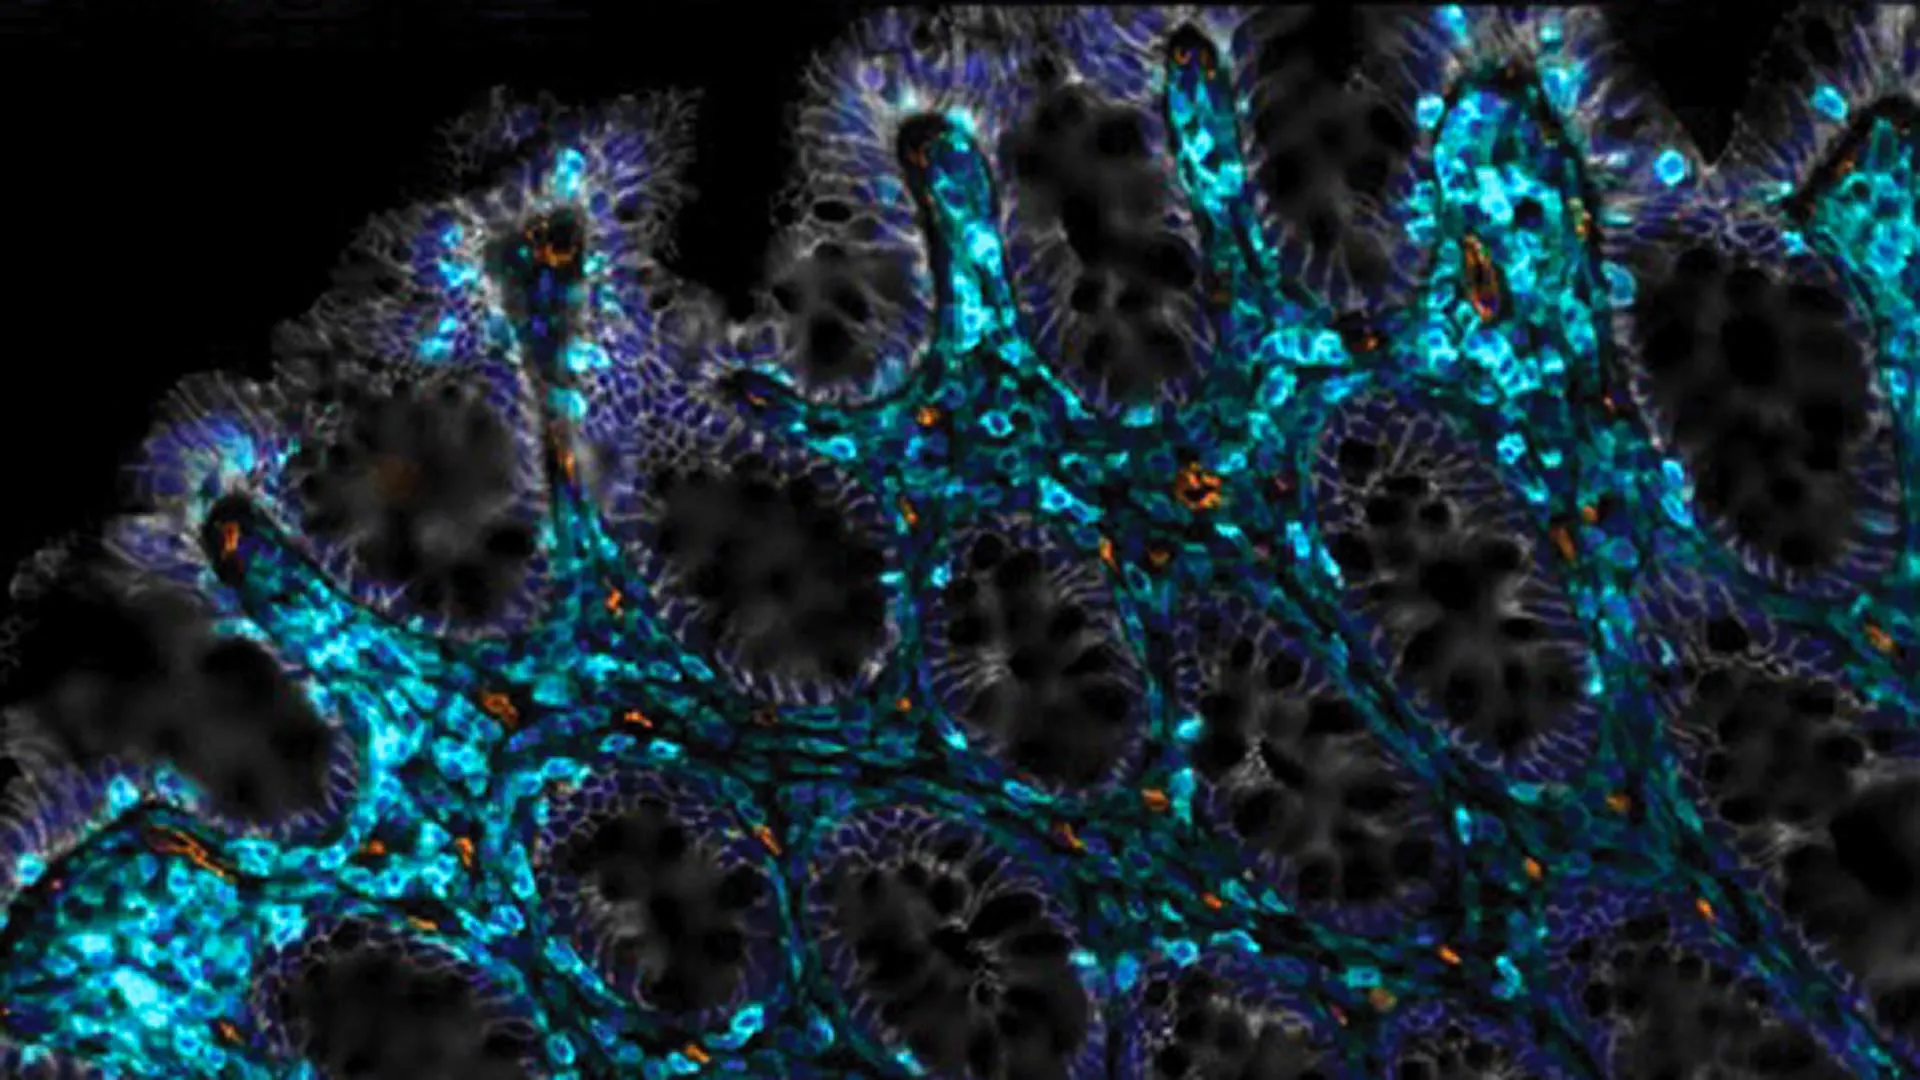

#BreastCancer #RiskAssessment #PersonalizedScreening

#BreastCancer #RiskAssessment #PersonalizedScreening